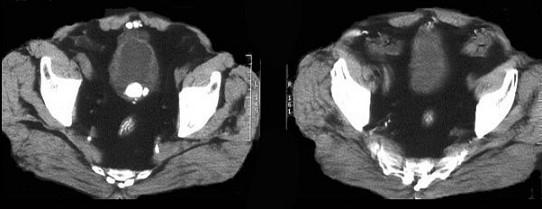

问题 男,11岁,1年来尿频、尿急、尿痛和排尿困难,尿流突然中断,改变体位又能继续排尿。应首先考虑 ( )

选项 A、膀胱结石 B、泌尿系结核 C、尿道炎 D、包茎 E、膀胱炎

答案 A